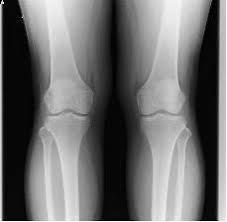

画像検査に頼りすぎる傾向です。

レントゲン検査は骨の形、変形などは調べれますが筋肉や筋膜組織は写りません。

鮮明な画像は撮れますが、狭い範囲を分析するに過ぎません。